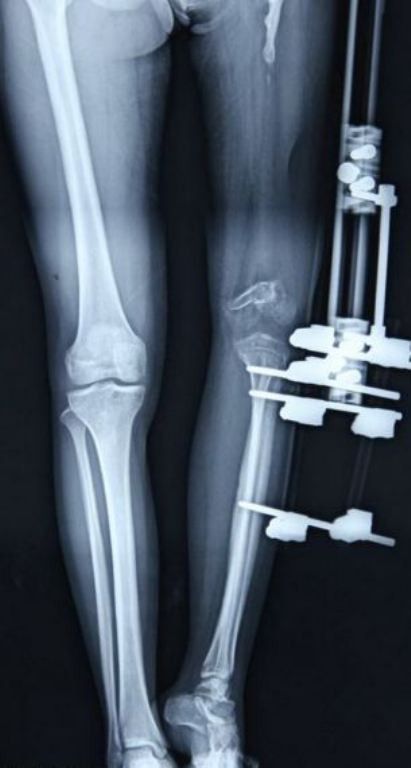

Ở giai đoạn thứ nhất, các bác sĩ đã gắn 1 khung kim loại vào chân của Xu và mỗi ngày cô gái trẻ phải nới thiết bị này một chút để kéo dài chân thêm 1 mm.

Sau một năm kéo dài chân, vào tháng 10/2013 Xu được phẫu thuật thay khớp gối và hông nhân tạo. Giai đoạn thứ hai này đã hoàn tất vào cuối tháng 2/2014 và các bác sĩ cho hay sau một vài tháng phục hồi chức năng, Xu sẽ có thể đi lại bình thường.